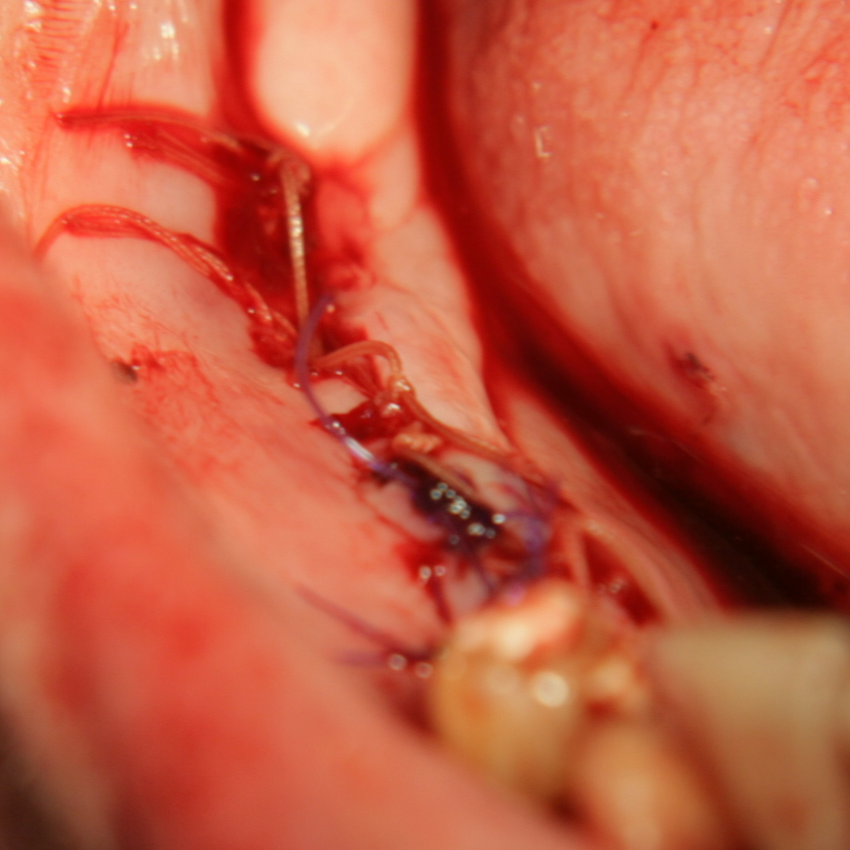

Титановите мембрани са твърди, ригидни приспособления, които се поставят в участъци с необходимост от увеличаване на костния обем - най-вече в областта на имплантологията, но също при радикуларни кисти и много рядко след екстракция на ретинирани мъдреци, при дефкетни фрактури, пострезекционни дефекти на челюстите, тежки остеомиелити и специфични възпаления на костта. Идеята на титановата мембрана е да предпази меките тъкани от колапс, поне за известен период от време, през който период под мембраната да започне костообразуване. През първите шест - осем месеца титановата мембрана оказва своя ефект, след което вече е безсмислено да остава в устата на пациента.

При операции с цел изграждане на допълнителн костна тъкан (костна пластика) винаги е добре да се перфорира кортикалната пластинка на костта. През тези перфорации излизат костни клетки, които постепенно прорастват в котозаместващия материал и синтезират нова костна тъкан. Перфорациите могат да се извършат с кръгло борче или с АСМ - фрезата на Neobiotech - Южна Корея.